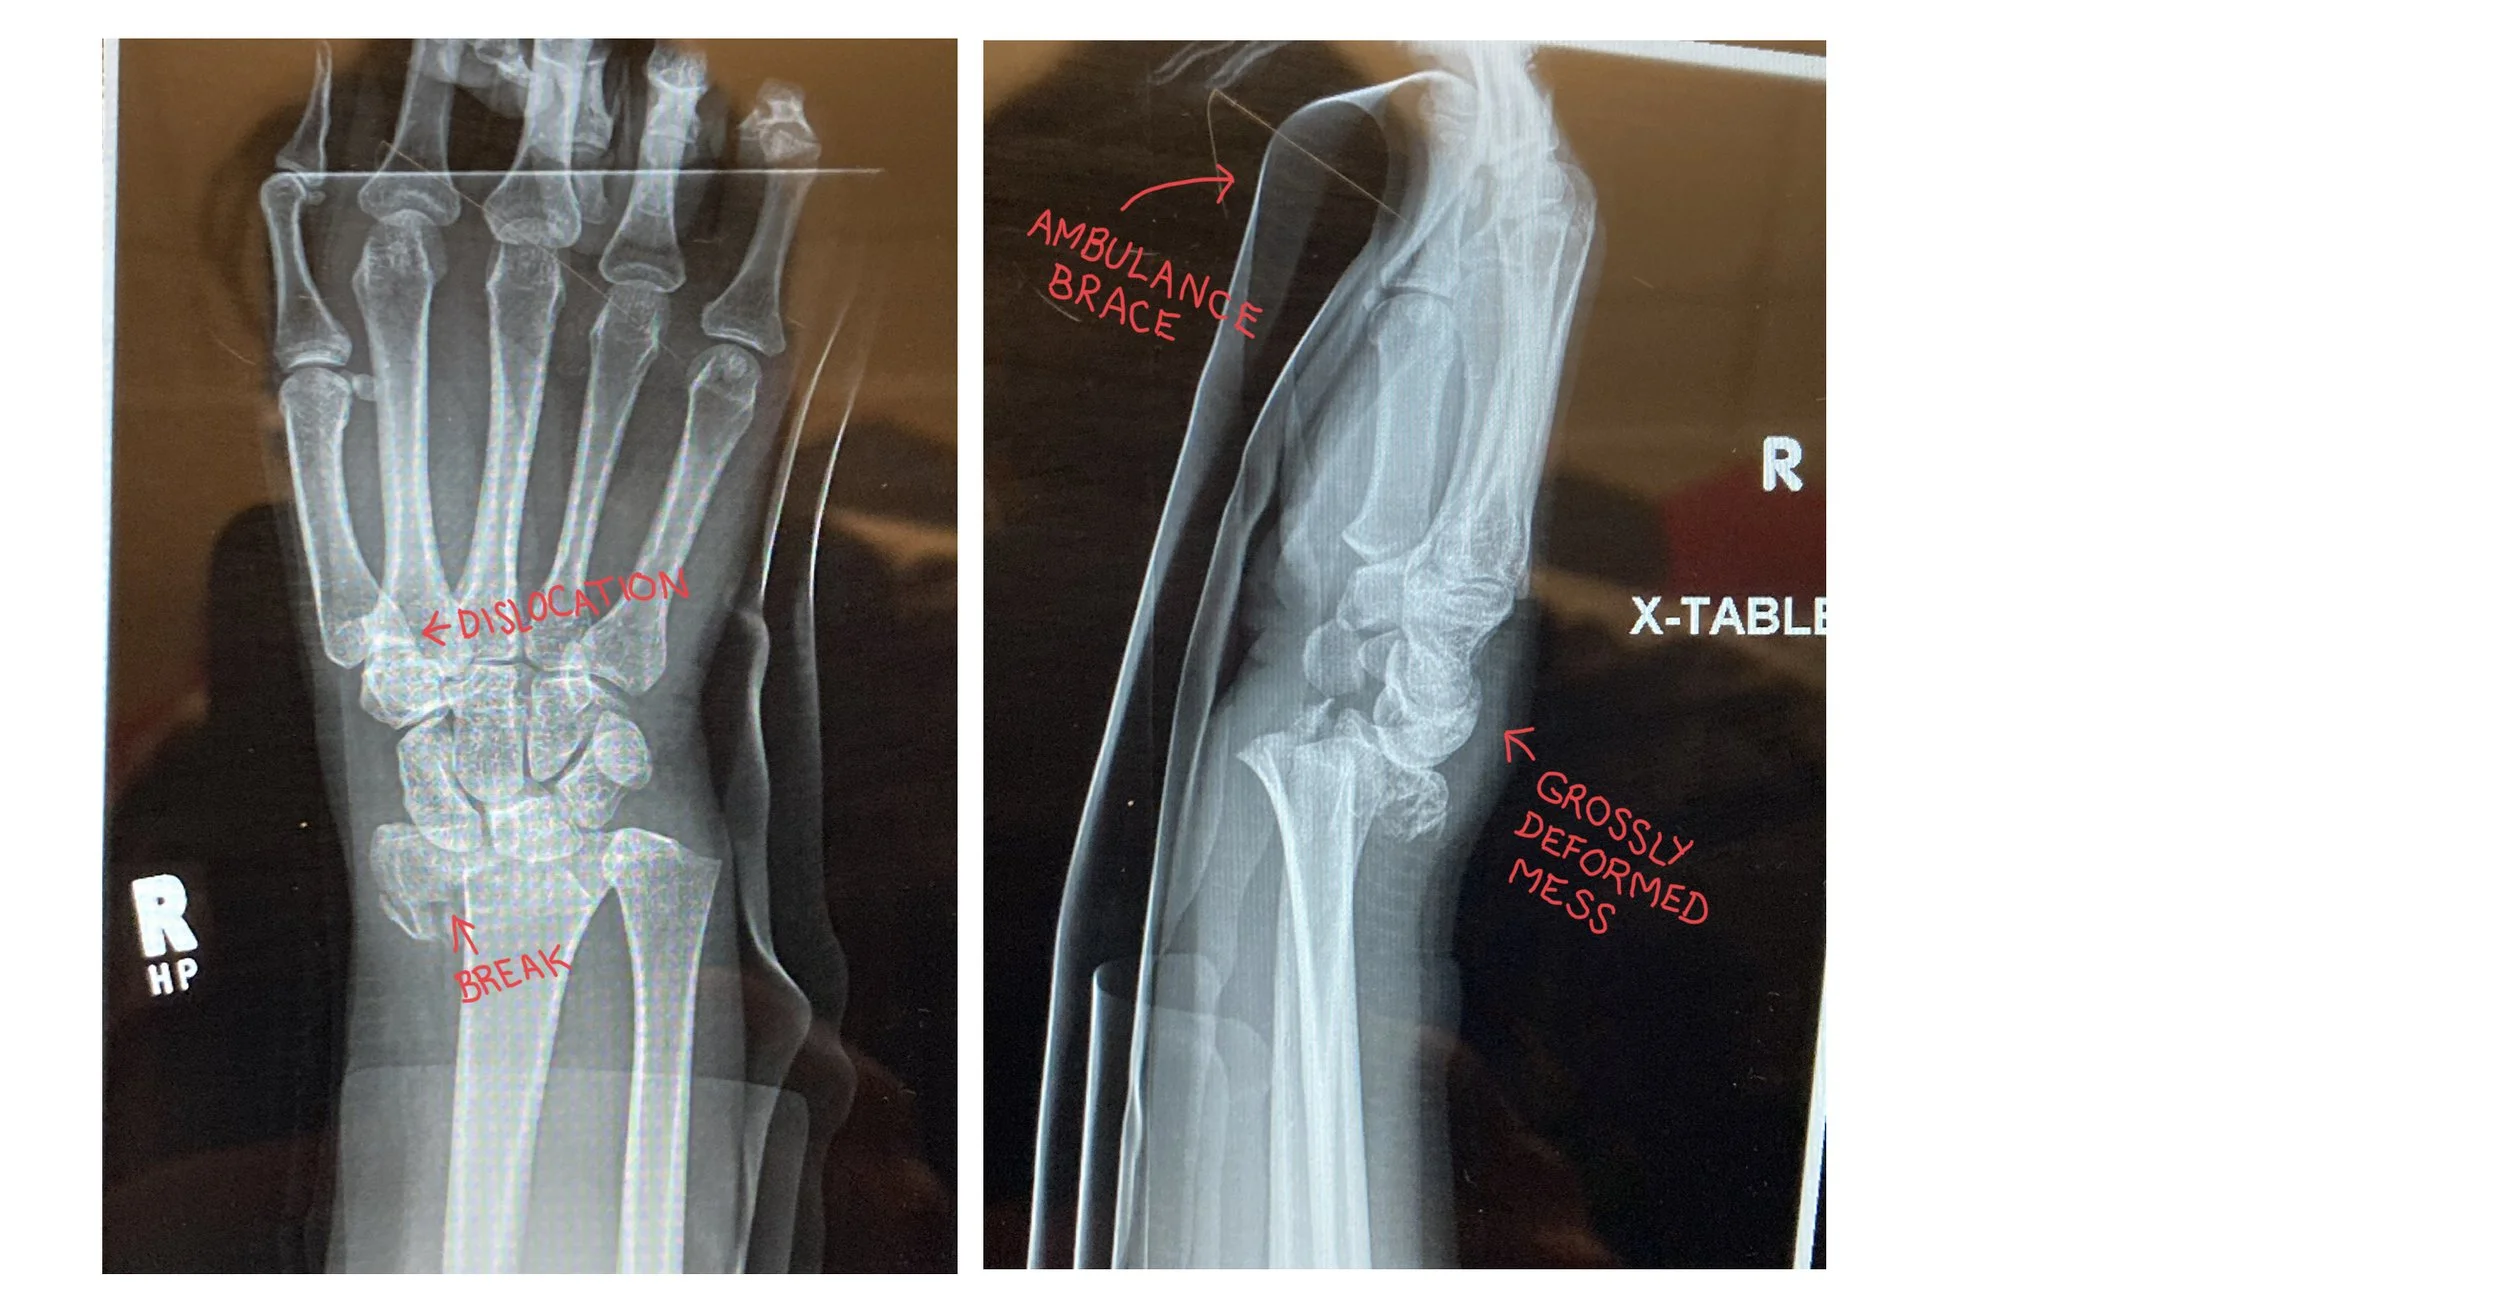

Eventually some of my people made it through the terrible road conditions to keep me company, and even more eventually I was sent for x-rays which confirmed that my wrist was very, very broken in addition to being “grossly deformed” (a term which I heard at least three times when the medical professionals were describing it to each other or to myself). The ER doctor also told me that he wasn’t sure whether surgery would be an option, because it would be “a bit like trying to screw gravel together”.

(Apologies for the reflections and satiations — the official copies didn’t arrive in time, so these were photographed from another screen because the program they were being viewed in blocks screen shots.)

Unlike in my edited doodle, there was not a single break, clean and easily fixable — there were multiple breaks, with one piece of bone sitting all alone, isolated from its friends, even after they sedated me and “reduced” it (we common folk usually say “set”). I am eternally grateful that I was 100% unconscious for that part.